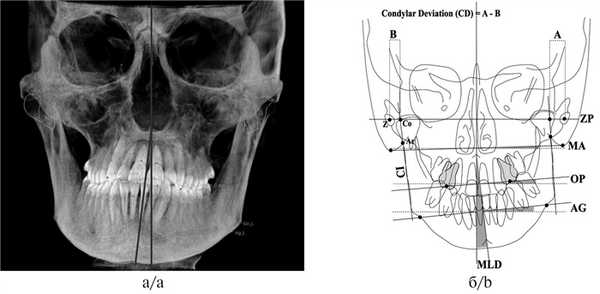

4. Оценка центральной линии. Несоответствие центральных линий челюстей возможно из-за смещения нижней челюсти в правую или левую сторону. На реформатах КЛКТ в окне цефалометрического анализа необходимо оценить показатель MLD (mandibular lateral displacement), который характеризуется образовавшимся углом между срединно-сагиттальной линией MRS, проходящей через точки Gl (Glabella — наиболее выступающая вперед в медиально-сагиттальном сечении точка на носовом отростке лобной кости, где лобная кость образует более или менее выраженную выпуклость), ANS — передняя носовая ость и Me (Menton — самая нижняя точка подбородочного симфиза — центр подбородка (рис. 3) [4].

Рис. 3. Оценка MLD нижней челюсти.

а — смещение влево [4]; б — смещение вправо.